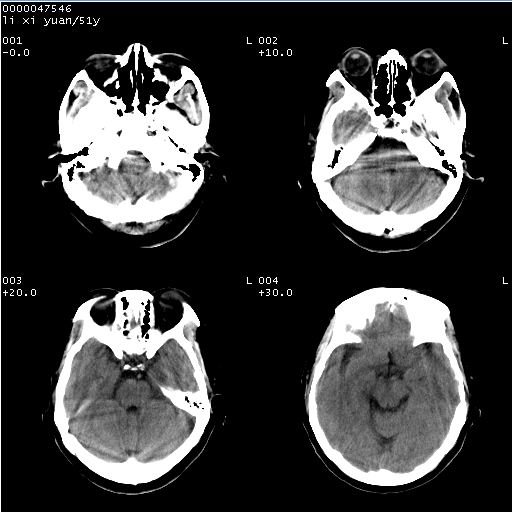

以下是引用余辉在2008-4-27 14:02:00的发言:[br]病灶位于中央沟前方?位于额叶?高密度灶,灶周水肿不明显,病灶似沿脑沟走行,强化明显,局部层面呈现环状强化,考虑1脑表面血管性疾病,如血管瘤,血管扩张,灶内血栓形成,其次考虑肿瘤如脑膜瘤、转移瘤,胶母等

以下是引用形影不离在2008-4-27 14:13:00的发言:[br]考虑胶质瘤可能性大,不排除慢性炎性肉芽肿。建议mri检查。